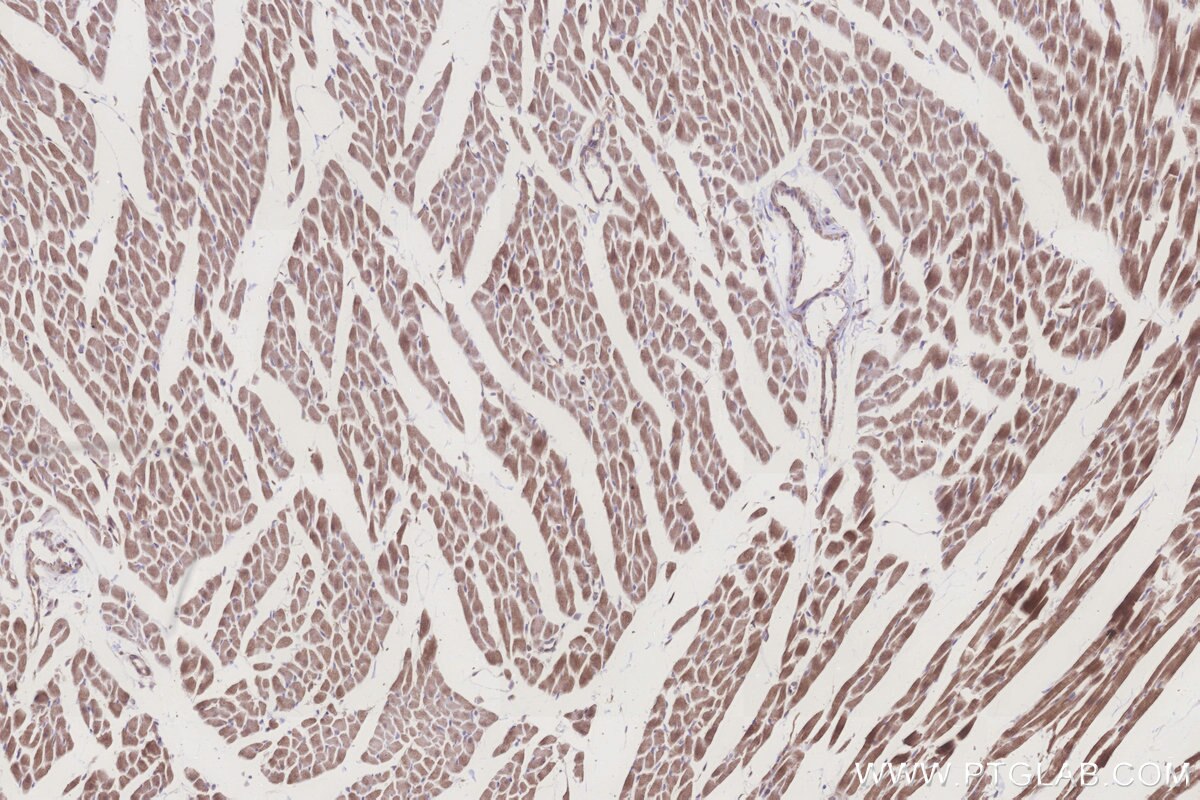

Validation Data Gallery

KHC3260 is a ready-to-use IHC kit for staining of ALDH1L2. The kit provides all reagents, from antigen retrieval to cover slip mounting, that require little to no diluting or handling prior to use. Simply apply the reagents to your sample slide according to the protocol and you're steps away from obtaining high-quality IHC data.